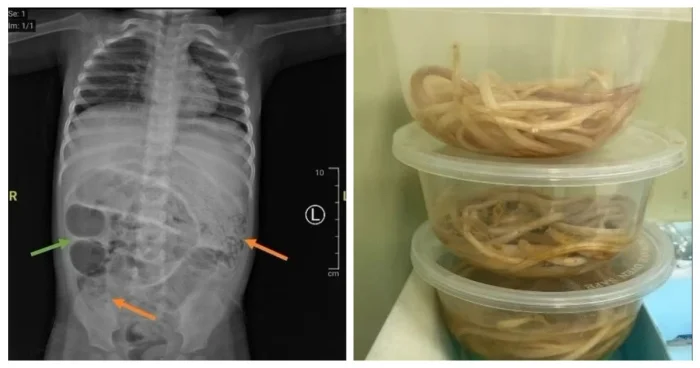

У маленького пациента начались рвотные позывы, в которых обнаружились черви, а рентгенологическое исследование желудка выявило серые образования, указывающие на «кишечную непроходимость».

Хирургическая команда выполнила лапаротомию — разрез брюшной полости — и нашла червей, блокирующих три участка тонкой кишки. Паразиты были извлечены и направлены в лабораторию для дальнейшего анализа.

Этот вид круглых червей, известный как аскарида, может достигать 35 сантиметров в длину и обитать в кишечнике человека.